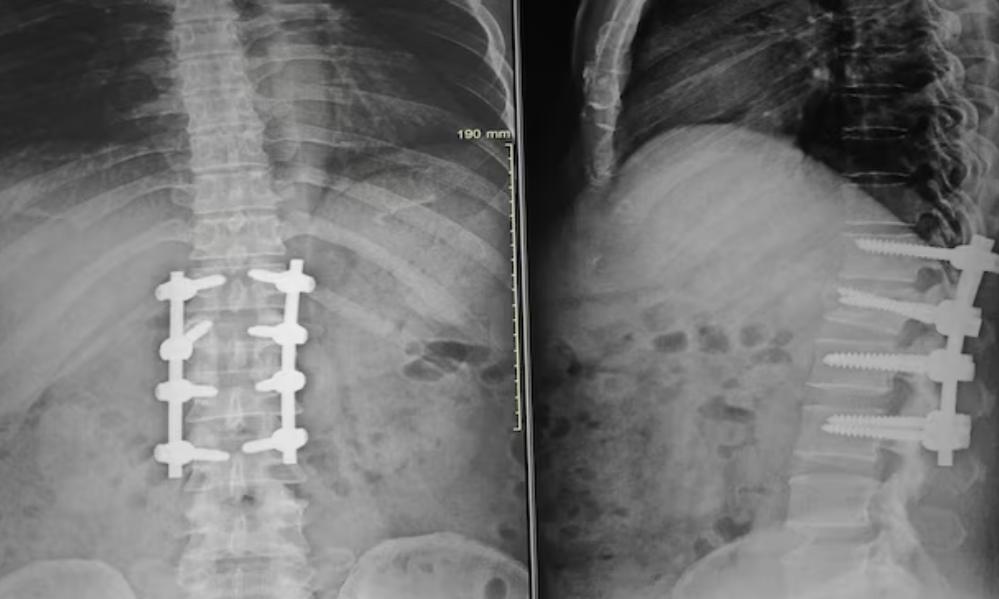

Scoliosis Correction Surgery in Balewadi – Understanding Treatment for Abnormal Spine Curvature

Scoliosis Correction Surgeon for Adult and Pediatric Patients in Balewadi

Best Scoliosis Surgery Specialist in Pune | Best Scoliosis Surgery Specialist in Baner |